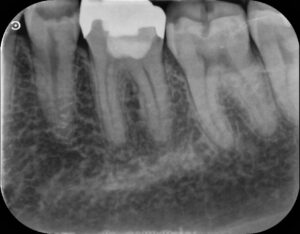

左上の前から4番目の歯です。不十分な根管治療が施されておりました。

根管治療を開始しました。(器具が根の先端まで到達しているかの確認のレントゲン写真です)

最終的なお薬を入れました。

お薬を詰め、プラスチックによる修復後1年1ヶ月経過後のレントゲン写真です。

レントゲン上でも炎症は認められず、歯茎の腫れ、痛みといった症状も認められません。

これからも定期的に経過を診ていきたいと思います。